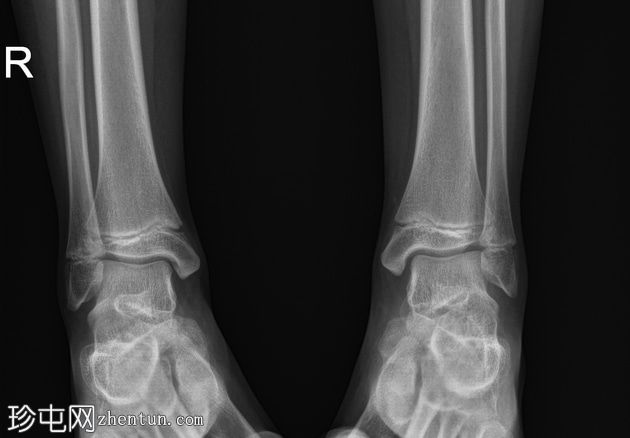

X线片

正位片

双侧跟骨密度增高,可见跟骨骨骺碎片,提示跟骨骨骺炎,又称塞弗氏病。

塞弗氏病,又称跟骨骨骺炎,是生长发育期儿童足跟(或跟骨)生长板后方的炎症。

该病被认为是由足跟反复受力引起的。这种疾病良性且常见,通常在生长板闭合后或活动量减少时缓解。